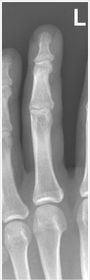

| What's the evaluation criteria for the PA Finger X-Ray? | ANATOMY: distal phalynx -> distal 1/2 of metacarpal demonstrated CRITERIA: - equal concavity on both sides of phalanges - IP and MCP open - no overlapping of adjacent fingers POSITIONING: CR perpendicular @ PIP joint |

| What's the evaluation criteria for the Lateral finger x-ray? | ANATOMY: entire digit demonstrated CRITERIA: open joint spaces concave to one side, while the dorsal side is straight no overlapping of adjacent fingers/soft tissues POSITIONING: CR perpendicular @ PIP joint |

| Oblique finger x-ray image criteria? | ANATOMY: entire digit demonstrated CRITERIA: more concavity to one side open joint spaces no superimposition of adjacent fingers POSITIONING: CR perpendicular @ PIP joint |